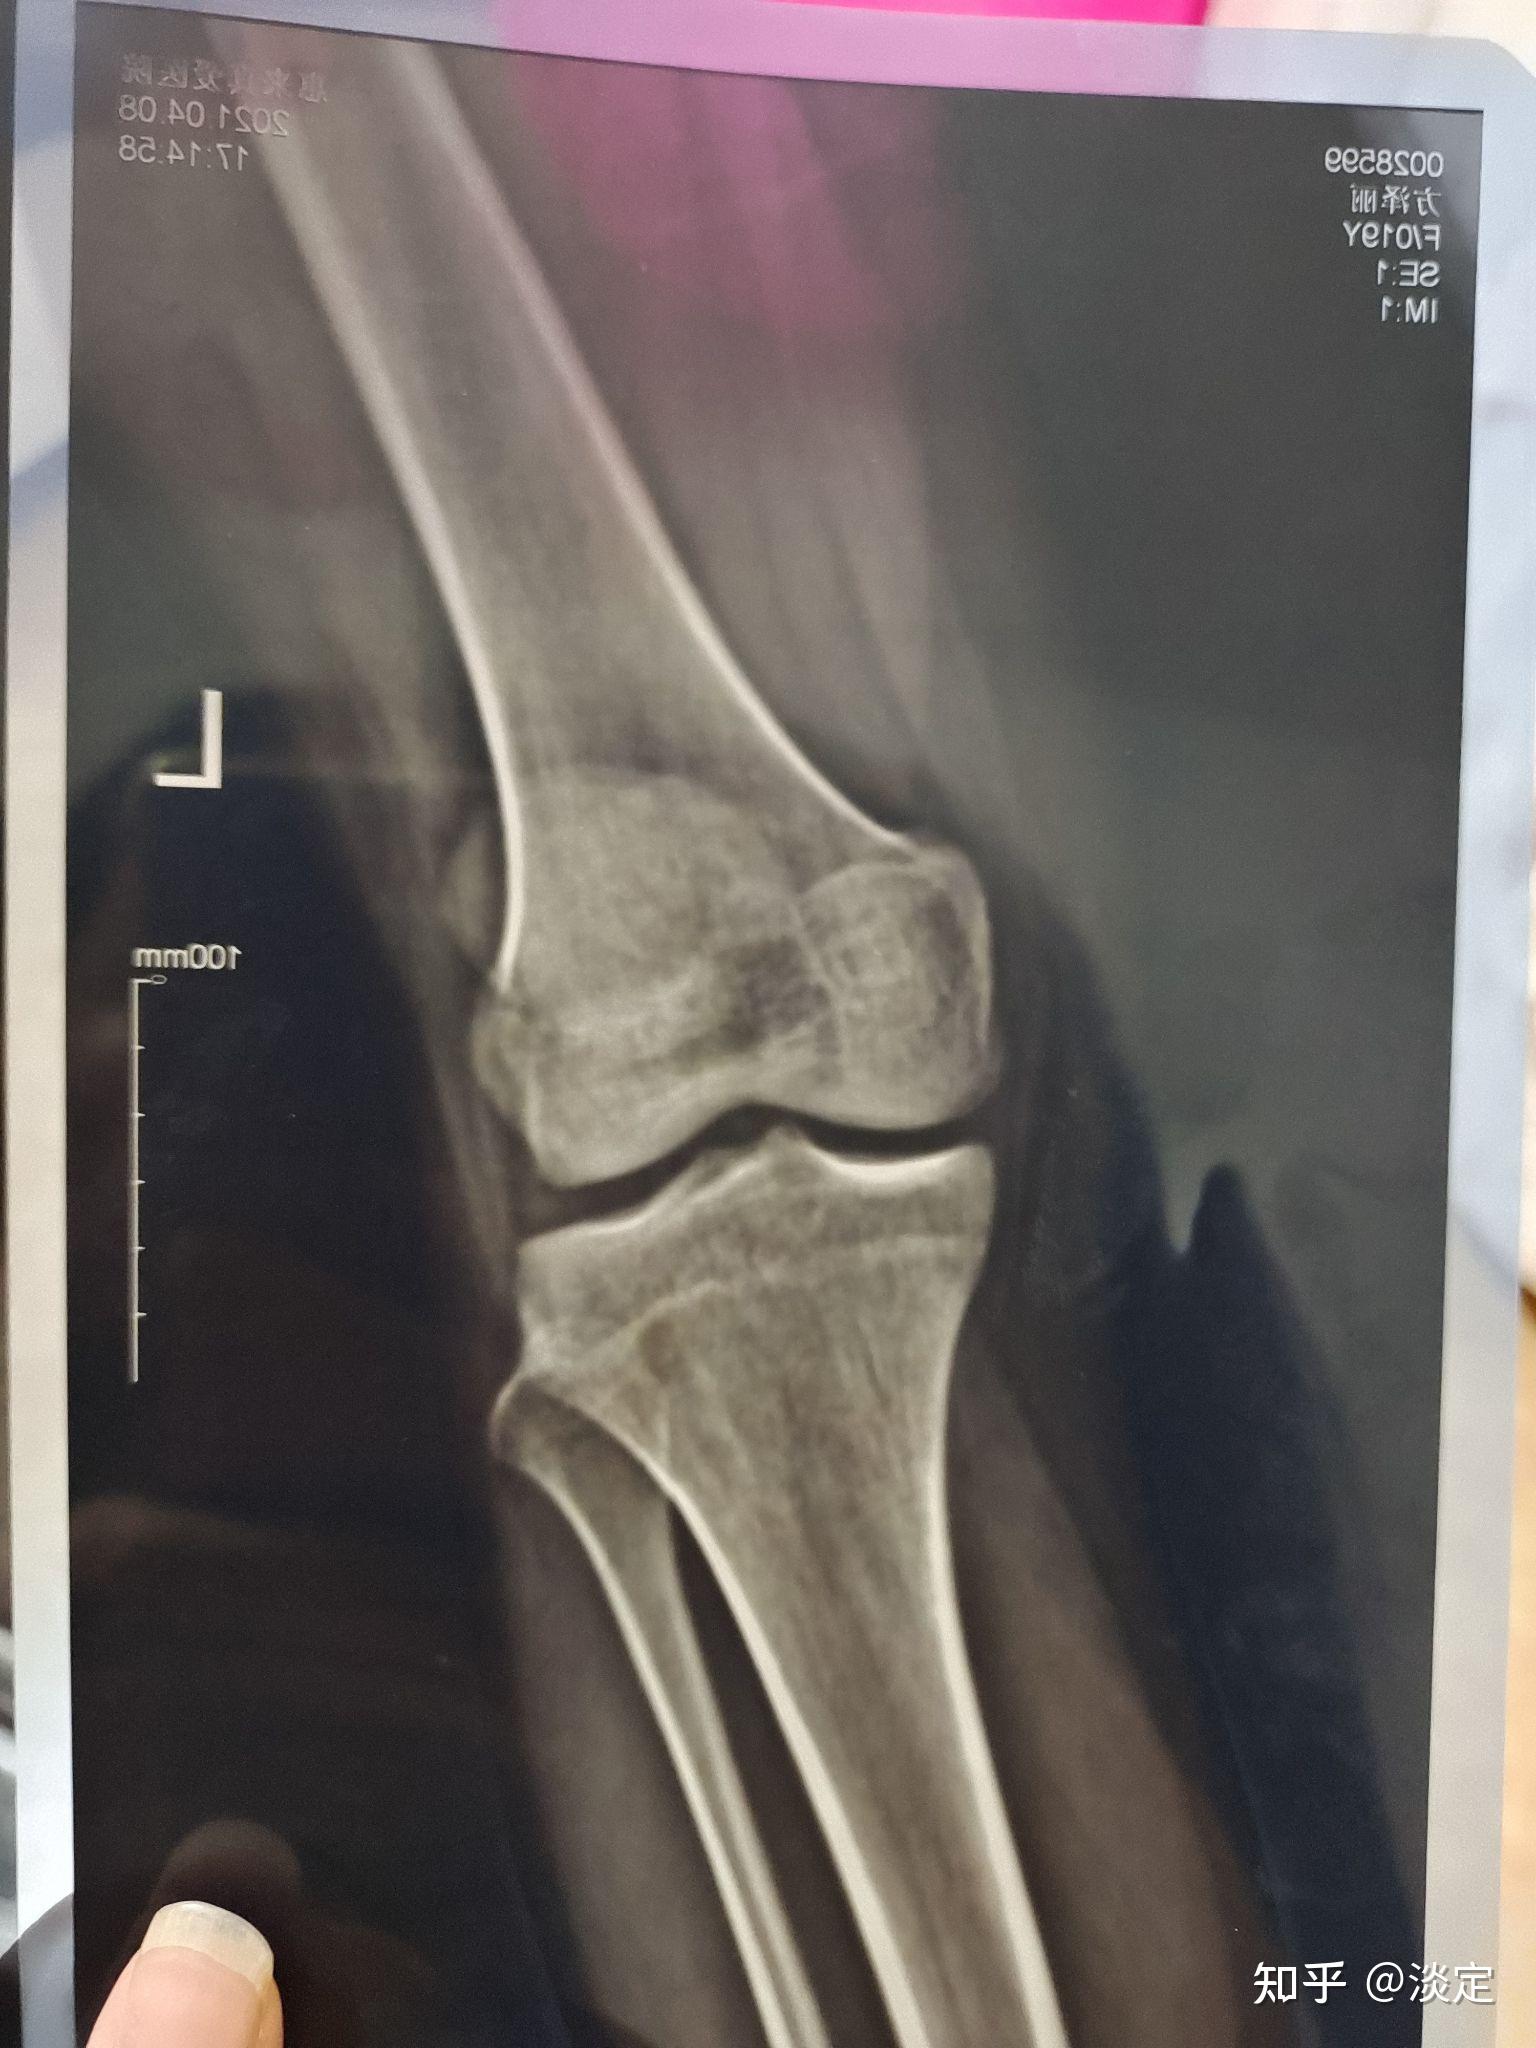

男孩,年龄17岁,去医院测骨密度拍了x光片(如图),请看看骨骼线是否闭合